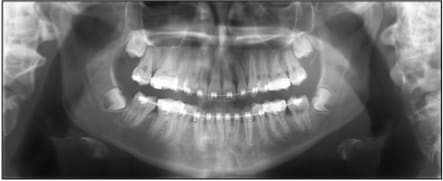

Si joint de illustration tiré de publication, juste pour montrer a notre amis alapex que si pour une raison X ou Y ont veut récupérer cette 8 c'est faisable, compliqué cher mais faisable.